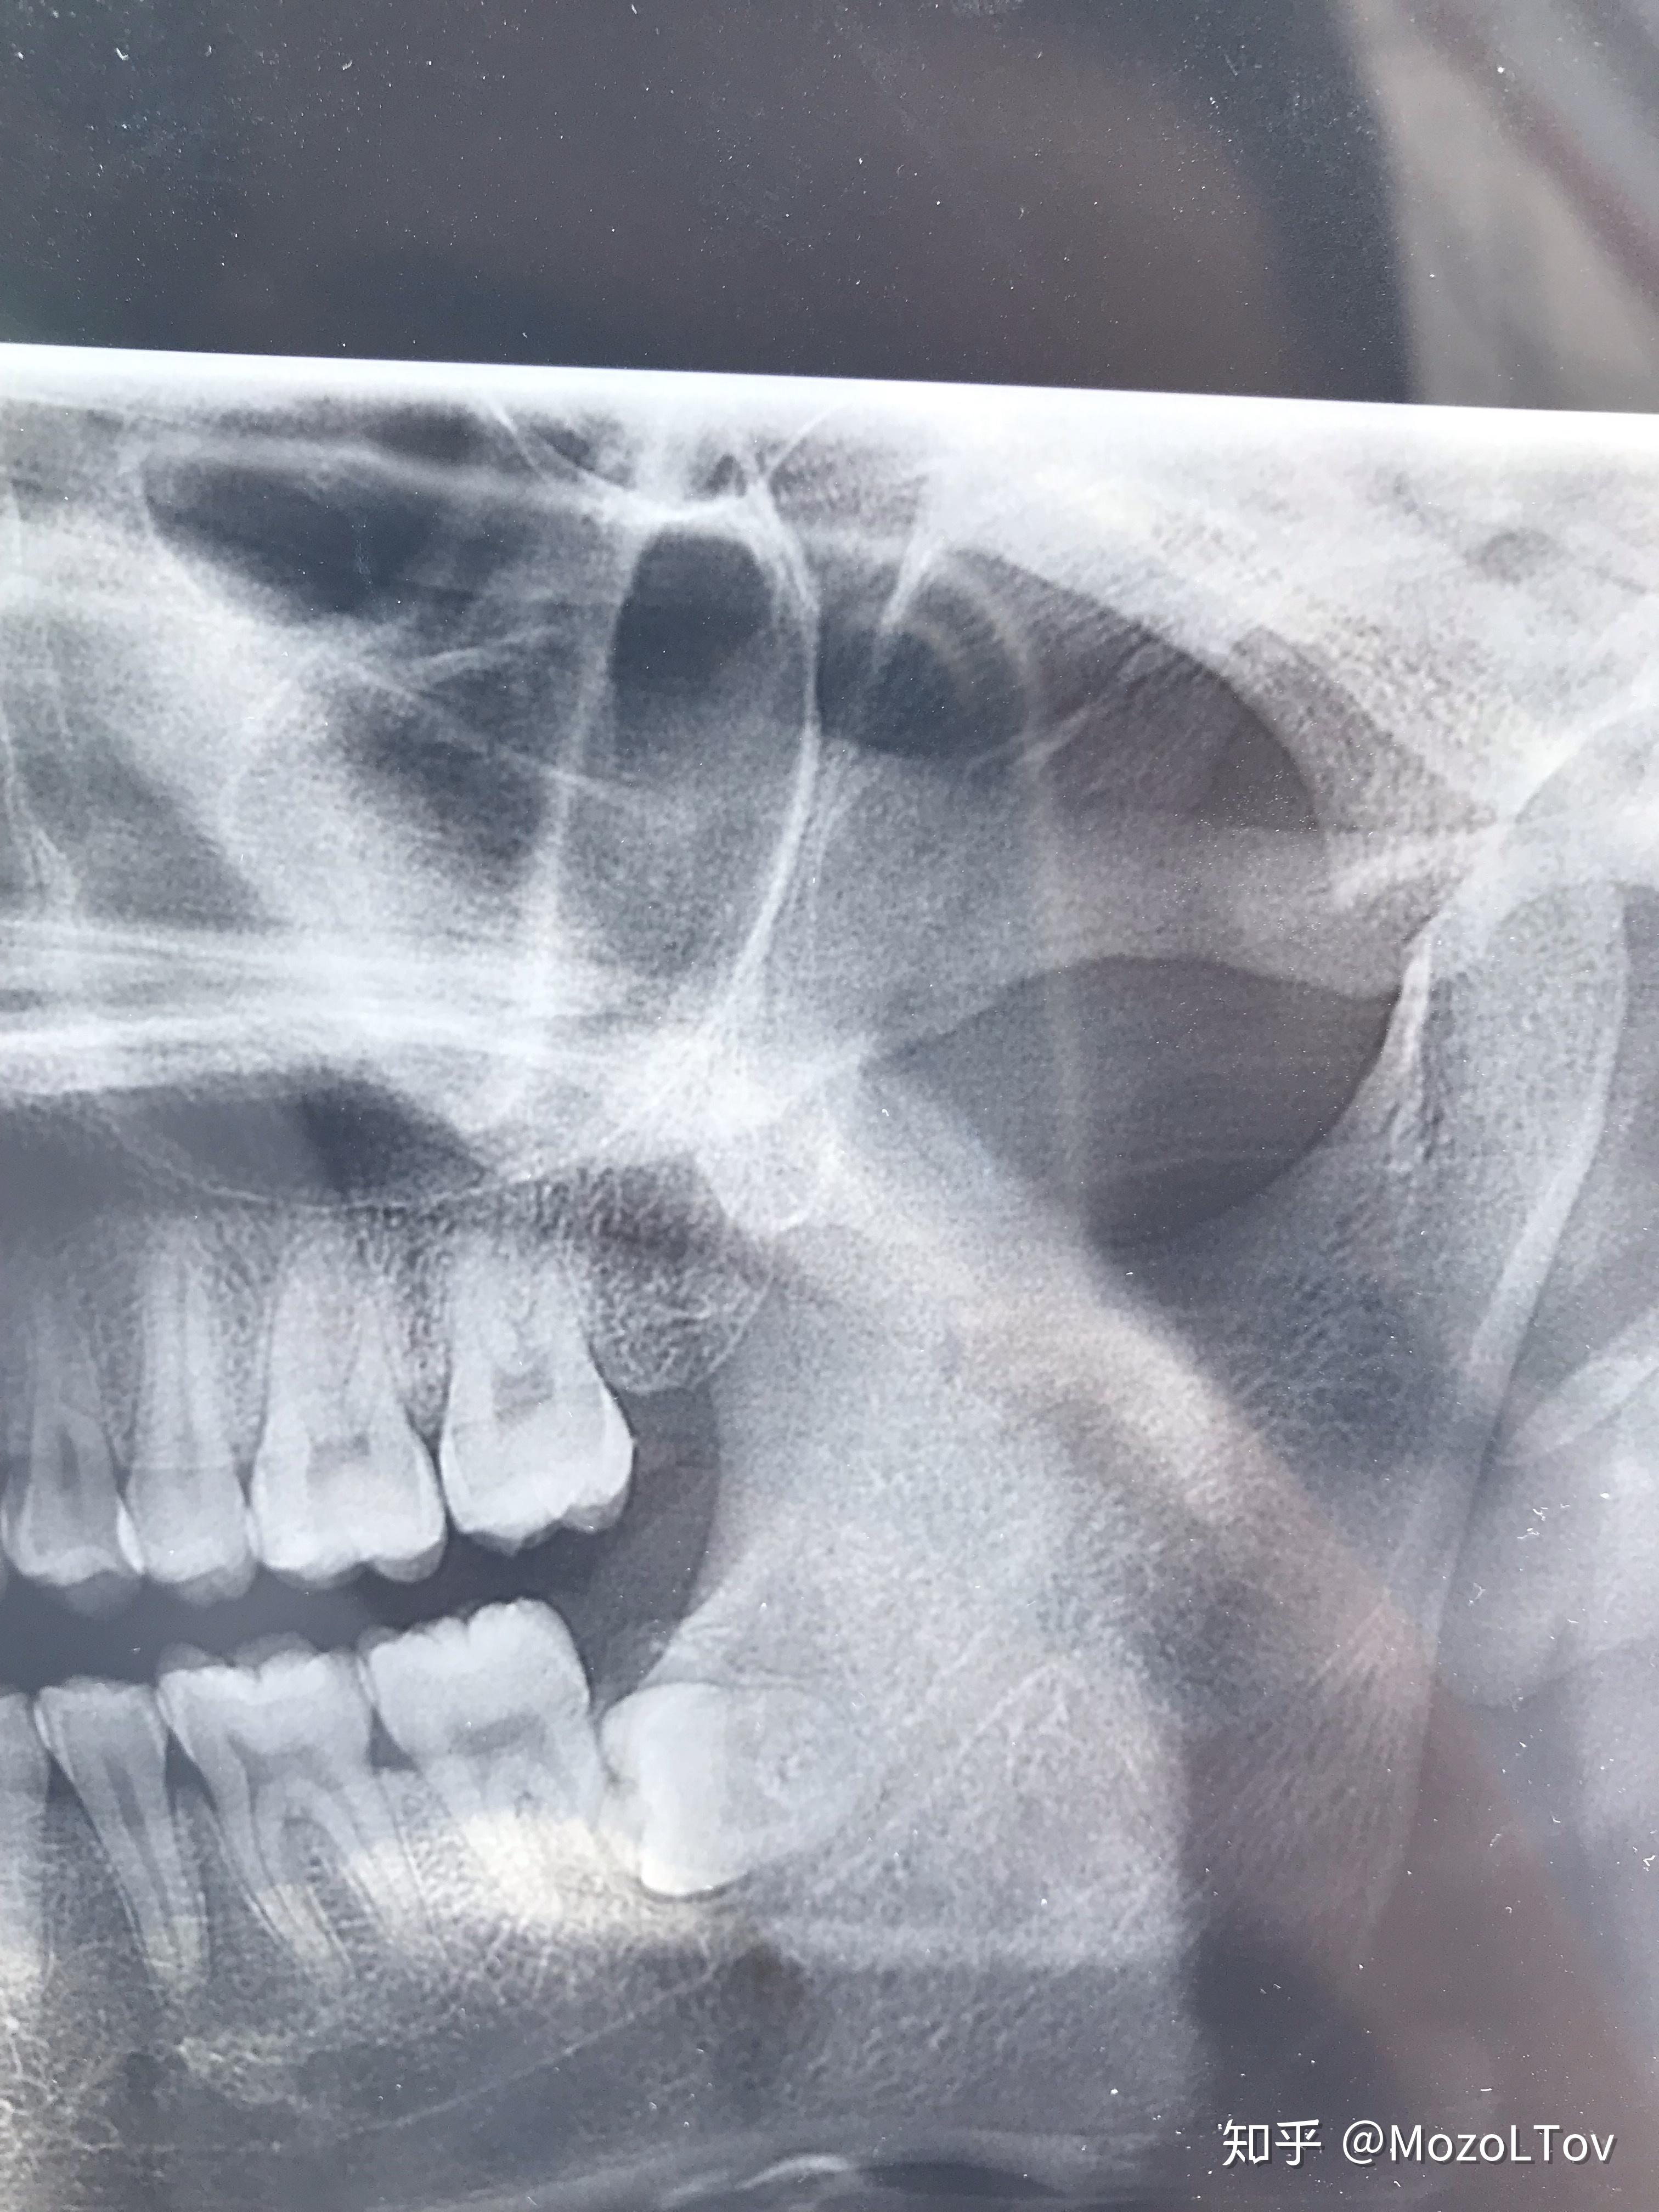

进来了就发一个牙片纪念一下我两个全包围横向阻生牙

下颌横向低位阻生智齿